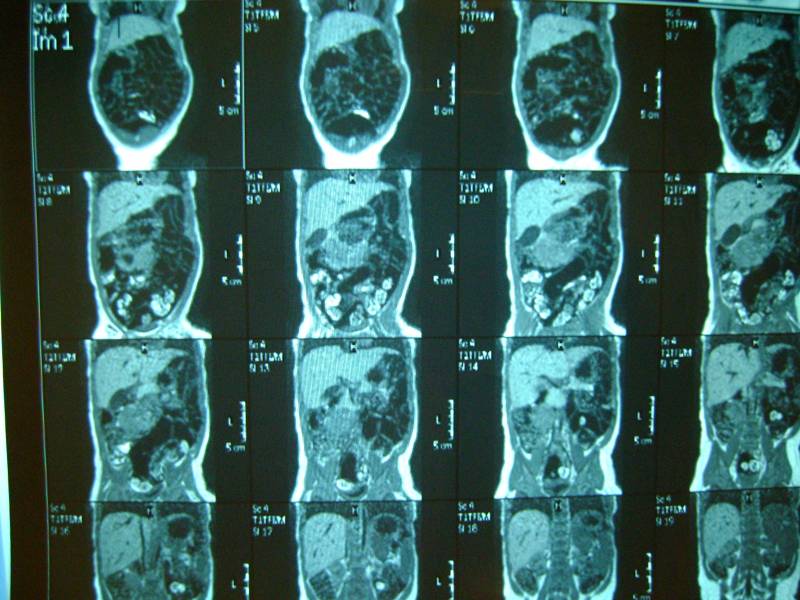

добавляем фото